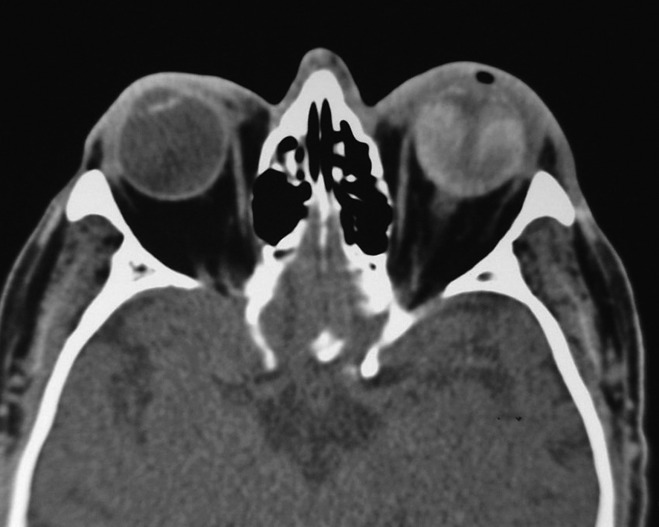

Retinal Detachment in Patients With Retained Lens Fragments or Lens Replacement Retinal Detachment if you have a retinal detachment, you may need surgery to reattach your retina to the back of your. Retinal tear surgery and retinal detachment surgery are distinct medical procedures. how is a detached retina diagnosed? The retina is a thin layer of light. retinal detachment occurs after a tear in the retina develops, allowing fluid to. Lens Replacement Retinal Detachment.